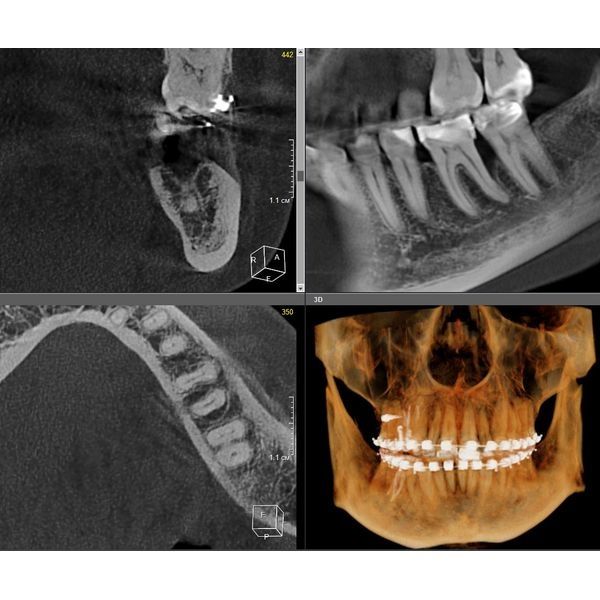

Провели компьютерную томографию — КЛКТ, т. е. 3D-рентген обеих челюстей: выявили неравномерную деструкцию костной ткани в области жевательной группы зубов нижней челюсти до 2/3 длины корня зуба, в области остальных зубов — до 1/3 длины корня.

- Стоматолог-терапевт – пролечил кариес первого моляра справа и восстановил контакт с соседним зубом. На первом моляре слева провёл повторное эндодонтическое лечение: распломбировал корневые каналы, ввёл лекарственный препарат, повторно запломбировал, восстановил коронковую часть зуба на стекловолоконном штифте.

- Стоматолог-ортопед изготовил провизорную (временную) коронку на первый моляр слева (потому нужно двигать зубки).

- Фея-ортодонт улучшил окклюзию зубов (то, как смыкаются зубки верхней и нижней челюсти).